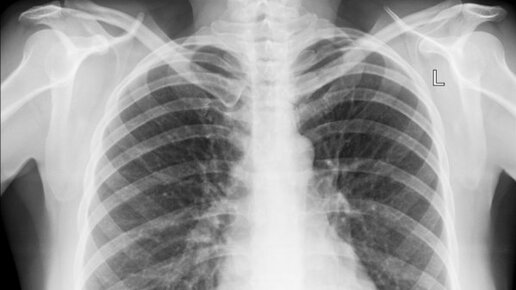

Вопрос “сколько раз в год можно делать рентген” звучит так, будто существует чёткий лимит — например, три раза можно, а четвёртый уже опасен. На самом деле всё устроено иначе. В медицине считают не количество процедур, а суммарную дозу облучения и её необходимость. Чтобы разобраться без паники, нужно понять, что такое рентгеновское излучение и какие дозы мы получаем в реальности. Любое ионизирующее излучение измеряется в миллизивертах (мЗв). Но важно помнить: мы живём в мире радиации постоянно. Земля, космос, воздух — всё даёт естественный фон...

Что такое рентген? В обыденной жизни мы за частую раз в год проходим такую процедуру как флюорограф. Флюорография –самый популярный вид рентгенологического исследования, метод применяется в профилактических целях и пройти его должен каждый раз в год. В детском возрасте разрешено проходить процедуру флюорографии с 15 лет. Рентген же это метод более чёткого исследования организма человека и проводится он только с назначения врача. Частота проведения процедуры так же контролируется и назначается врачом,...